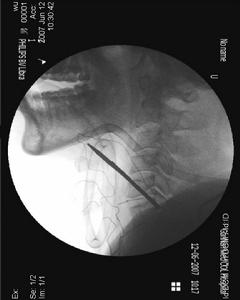

頸椎病又稱頸椎綜合徵,是頸椎骨關節炎、增生性頸椎炎、頸神經根綜合徵、頸椎間盤脫出症的總稱,是一種以退行性病理改變為基礎的疾患。主要由於頸椎長期勞損、骨質增生,或椎間盤脫出、韌帶增厚,致使頸椎脊髓、神經根或椎動脈受壓,出現一系列功能障礙的臨床綜合徵。表現為頸椎間盤退變本身及其繼發性的一系列病理改變,如椎節失穩、鬆動;髓核突出或脫出;骨刺形成;韌帶肥厚和繼發的椎管狹窄等,刺激或壓迫了鄰近的神經根、脊髓、椎動脈及頸部交感神經等組織,並引起各種各樣症狀和體徵的綜合徵。

頸椎病頸椎病發病機理:1、頸椎退行性改變:隨著年齡的不同階段發展,頸椎及椎間盤可發生不同的改變,在頸椎體發生退行性改變的同時,椎間盤也發生相應改變。2、外傷因素:在椎間盤退變的基礎上,進行劇烈活動或不協調的運動。3、慢性勞損:長期處於不良的勞動姿勢,椎間盤受到來自各種方面的牽拉、擠壓或扭轉。4、寒冷、潮濕:尤其在椎間盤退變的基礎上,受到寒冷、潮濕因素的影響,可造成局部肌肉的張力增加,肌肉痙攣,增加對椎間盤的壓力,引起纖維環損害。

頸椎病的基本病理變化是椎間盤的退行性變。頸椎位於頭顱與胸廓之間,頸椎間盤在承重的情況下要做頻繁的活動,容易受到過多的細微創傷和勞損而發病。其主要病理改變是:早期為頸椎間盤變性,髓核的含水量減少和纖維環的纖維腫脹、變粗,繼而發生玻璃樣變性,甚至破裂。頸椎間盤變性後,耐壓性能及耐牽拉性能減低。當受到頭顱的重力和頭胸間肌肉牽拉力的作用時,變性的椎間盤可以發生局限性或廣泛性向四周隆突,使椎間盤間隙變窄、關節突重疊、錯位,以及椎間孔的縱徑變小。由於椎間盤的耐牽拉力變弱,當頸椎活動時,相鄰椎骨之間的穩定性減小而出現椎骨間不穩,椎體間的活動度加大和使椎體有輕度滑脫,繼而出現後方小關節、鉤椎關節和椎板的骨質增生,黃韌帶和項韌帶變性,軟骨化和骨化等改變。由於頸椎間盤向四周膨隆,可將其周圍組織(如前、後縱韌帶)及椎體骨膜掀起,而在椎體與突出的椎間盤及被掀起的韌帶組織之間形成間隙,稱"韌帶間盤間隙",其中有組織液積聚,再加上微細損傷所形起的出血,使這種血性液體發生機化然後鈣化、骨化,於是形成了骨贅。椎體前後韌帶的鬆弛,又使頸椎不穩定,更增加了受創傷的機會,使骨贅逐漸增大。骨贅連同膨出的纖維環,後縱韌帶和由於創傷反應所引起的水腫或纖維疤痕組織,在相當於椎間盤部位形成一個突向椎管內的混合物,就可能對脊神經或脊髓產生壓迫作用。鉤椎關節的骨贅可從前向後突入椎間孔壓迫神經根及椎動脈。椎體前緣的骨贅一般不會引起症狀,但文獻上也有這種前骨贅影響吞咽或造成嘶啞的報告。脊髓及神經根受壓後,開始時僅為功能上的改變,如不及時減輕壓力,逐漸會產生不可逆的變化。因此如果非手術治療無效,應及時進行手術治療。